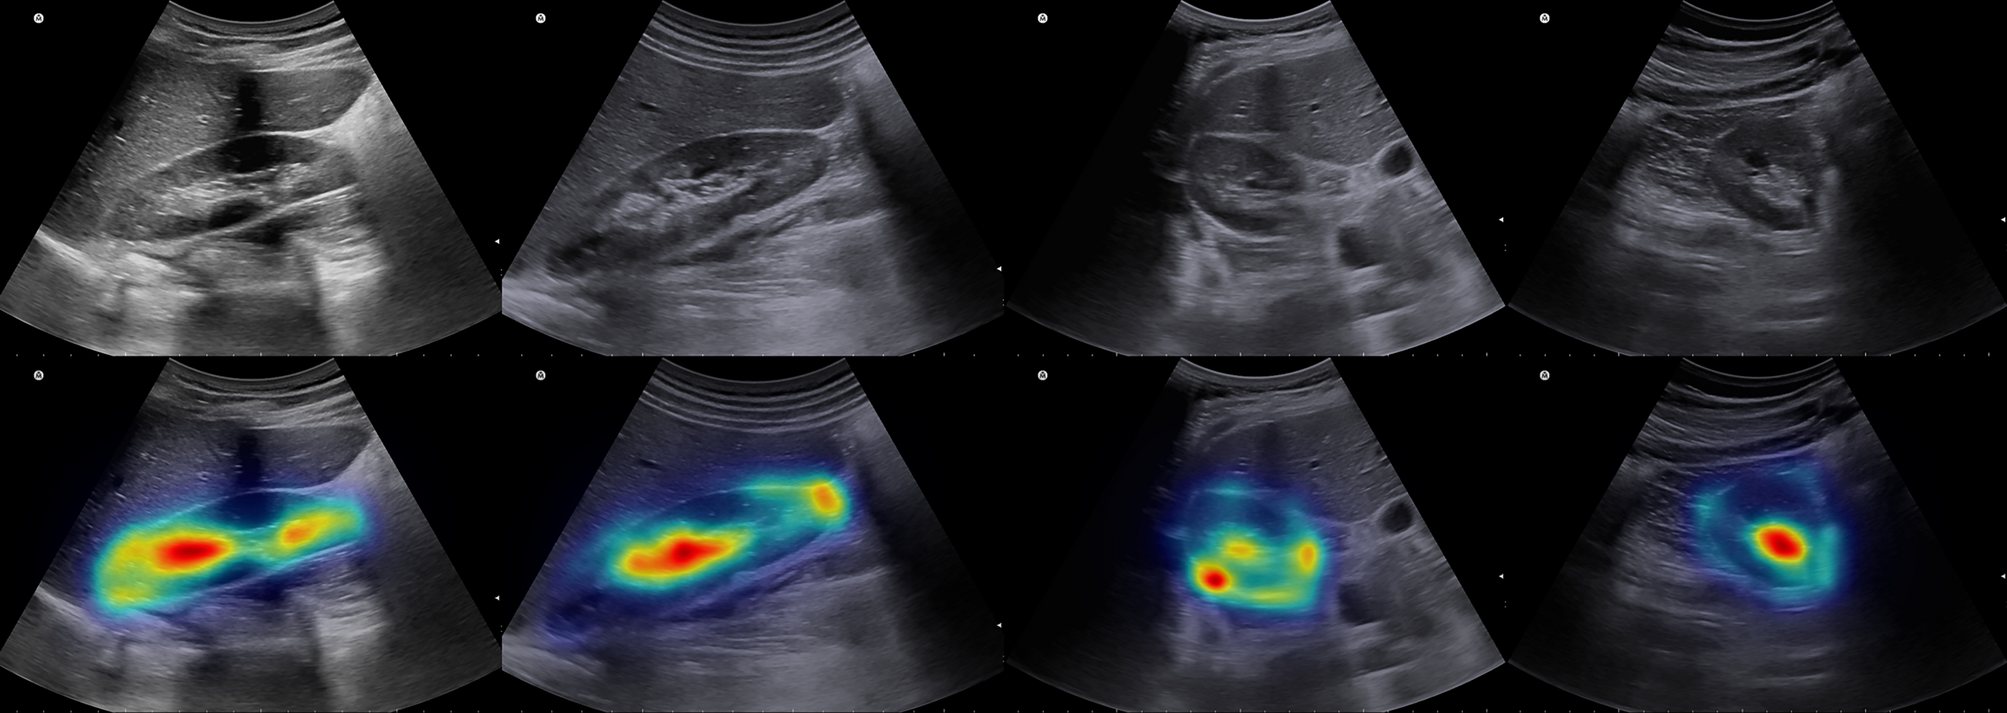

Figure 5

From: Fully automated kidney image biomarker prediction in ultrasound scans using Fast-Unet++

Grad-CAM analysis results in some samples of sagittal and axial images. Top row is the original images and bottom row is the resulted grad-CAM analysis.